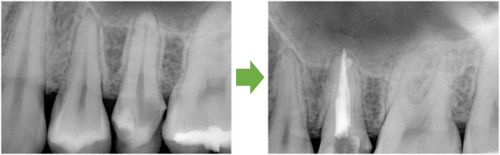

抜髄 左の前歯 川口の歯科 歯医者 さかえ歯科クリニック

2014年12月16日